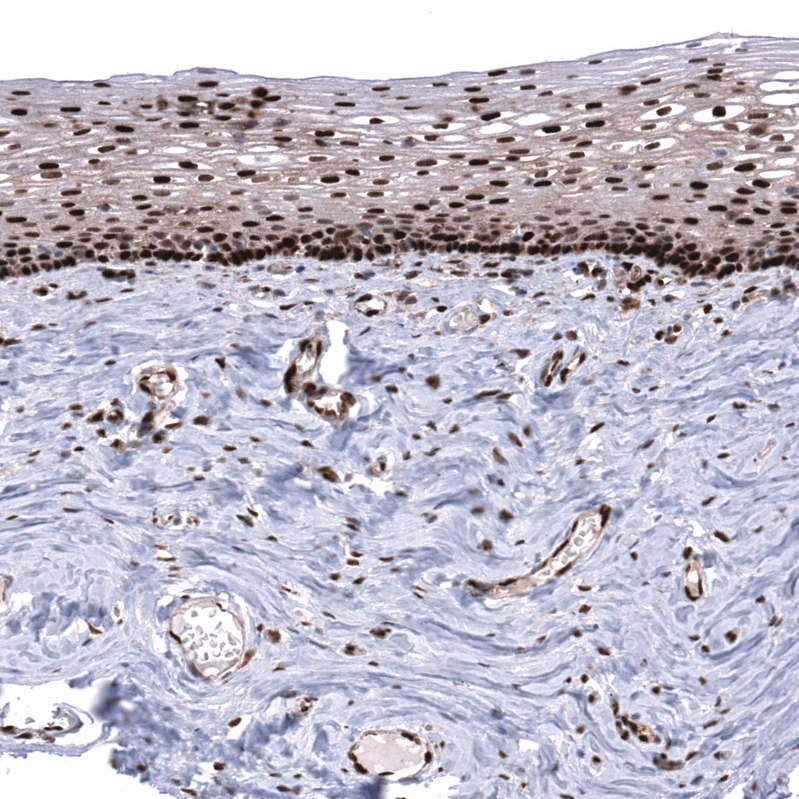

Immunohistochemical staining of human uterine cervix shows strong nuclear positivity in squamous epithelial cells.